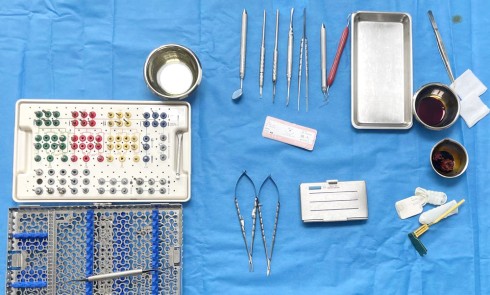

Nous proposons de retirer la couronne et le pilier implantaire, d’effectuer une greffe de tissu conjonctif enfouie afin d’améliorer le volume du tissu kératinisé péri-implantaire [5] et de procéder à la pose d’une couronne provisoire transvissée (fig. 3a à h).